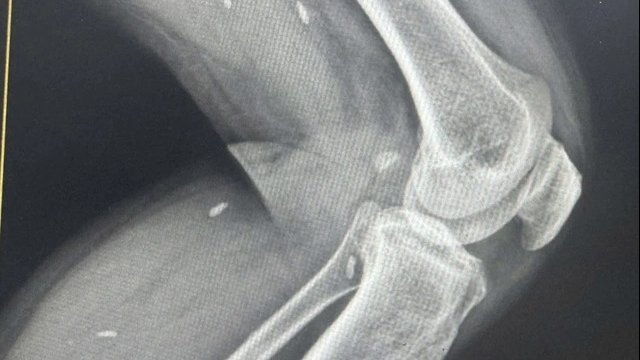

Sau khi thăm khám lâm sàng, bệnh nhân được chỉ định thực hiện xét nghiệm máu, chụp X - quang phổi, nội soi tai - mũi - họng. Kết quả chụp X-quang phổi phát hiện hình ảnh đám mờ ở đáy phổi phải, bác sĩ bệnh viện Hồng Ngọc đã chẩn đoán bệnh nhân cần theo dõi bệnh viêm phổi cấp. Ngay lập tức lúc 15h40 phút Bệnh viện đã làm thủ tục chuyển ngay tới Bệnh viện Nhiệt đới Trung ương cơ sở 2 bằng xe cấp cứu chuyên dụng được Bệnh viện bố trí riêng các trường nghi nhiễm Covid, theo đúng quy định của Sở Y tế.